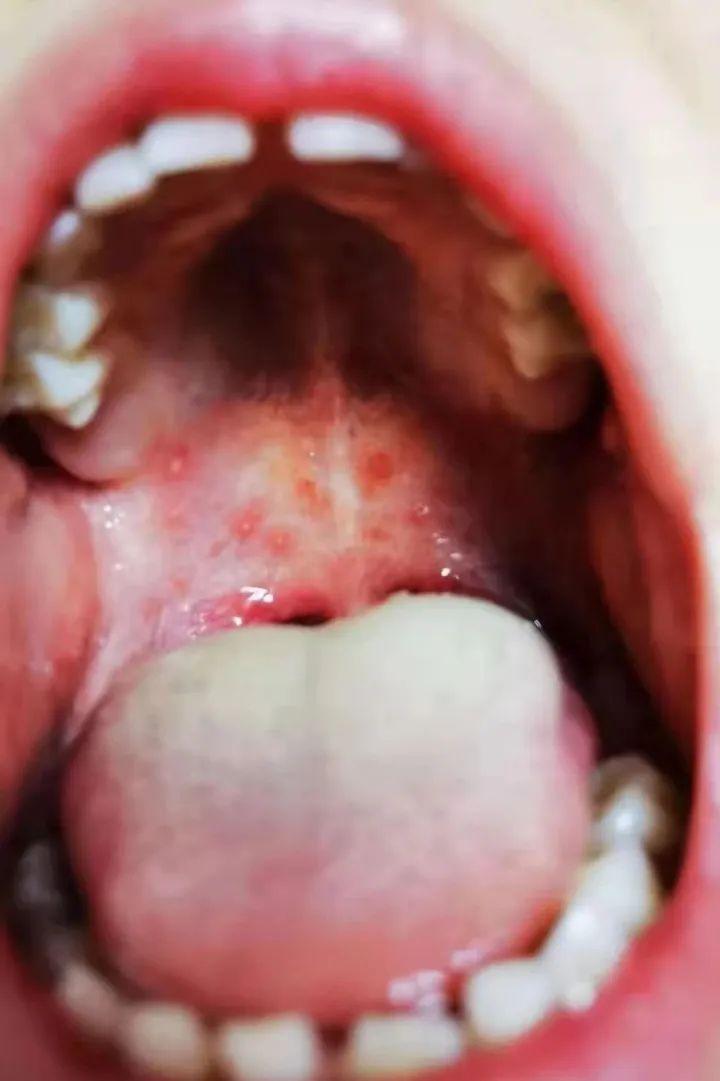

06 疱疹性咽峡炎/手足口病

病因:疱疹病毒感染引起的。

特征:口腔的上颚许多红色水泡,舌苔很厚,有时候舌头上也有疱疹,考虑疱疹性咽峡炎。如果口腔疱疹+手心+足心都有疱疹,考虑手足口病。

治疗:对症治疗,通常不需要使用抗生素治疗,也没有特异性抗病毒药物,多数孩子在 1 周后自行恢复。喉咙痛、高热可以吃对乙酰氨基酚或布洛芬,多喝水,口腔注意卫生。